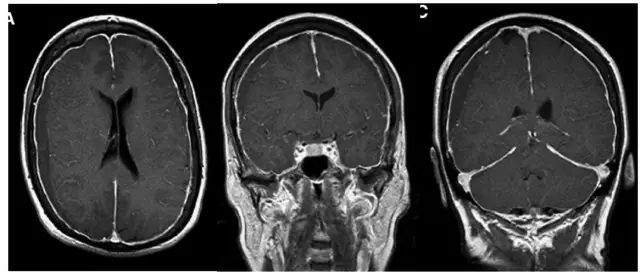

但术后2天再次出现头痛,不能缓解,5月2日复查头颅MRI提示硬膜下血肿术后复发,伴小脑下坠,脑沟及小脑上方仍可见较多脑脊液,四脑室变小,颅内静脉系统扩张明显(箭头所示见横窦扩张)(图3)。

图3. 术后1周(5月2日)复查头颅MRI显示左侧硬膜下血肿术后复发,伴小脑下坠,脑沟及小脑上方仍可见较多脑脊液,四脑室变小,颅内静脉系统扩张明显(箭头所示见横窦扩张)。

除了临床特异性的表现外,在影像学方面,SIH患者的颅脑MRI有5个典型特征(SEEPS):

(1)Subduralfluid collections硬膜下积液;

(2)Enhancement of the pachymeninges硬脑膜强化;

(3)Engorgement of venous structures静脉结构充盈 ;

(4)Pituitaryhyperemia垂体充血;

(5)Sagging of the brain脑组织下沉。其中又以硬脑膜强化及硬膜下积液最为常见。

针对本例患者,临床治疗中从一开始就忽视了体位性头痛这一核心症状,误以为是单纯的慢性硬膜下血肿;该患者最初的头颅MRI检查可以发现硬膜下血肿量较少,占位效应不明显,血肿与症状不符,在第一次钻孔引流术后复查的头颅磁共振可见硬脑膜静脉窦扩张、双侧硬膜下积液、脑室缩小、小脑结构移位下沉等特征性影像学表现,高度提示了自发性低颅压的可能;但因该疾病在神经外科相对少见,临床医生认识不足,最终未能及时诊断及治疗。